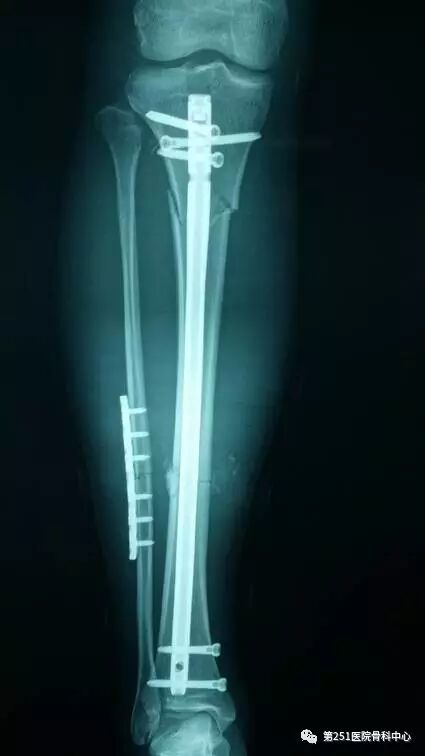

病例1:男性,40岁,车祸伤,胫腓骨多段骨折。